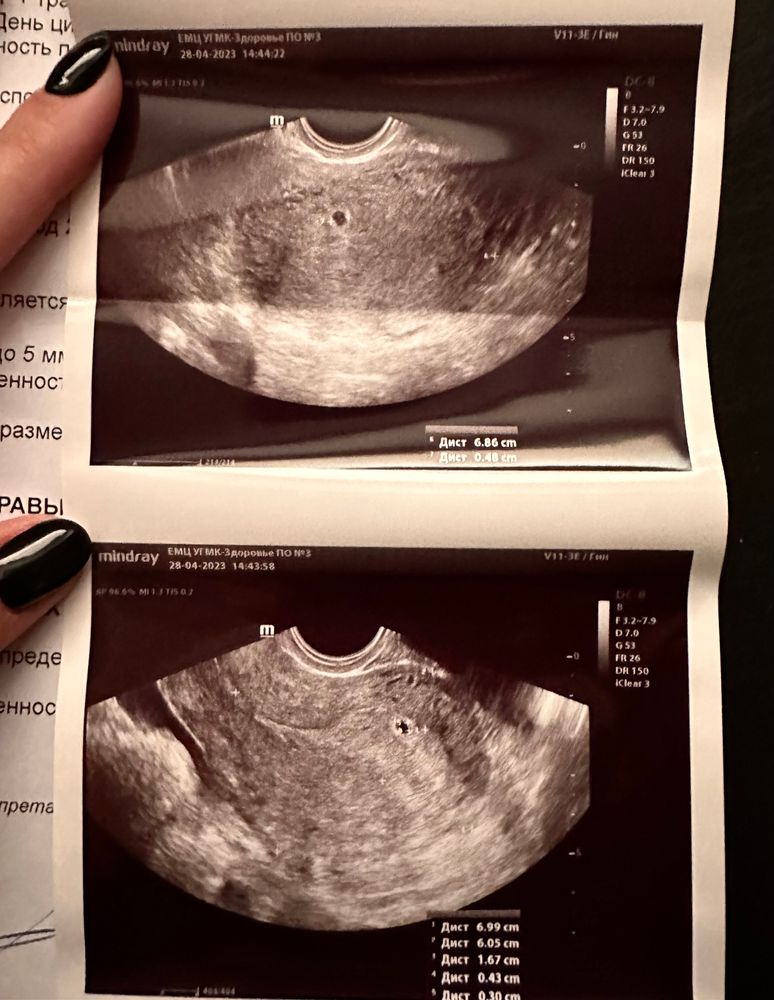

Правда срок поставили меньше 5+2.